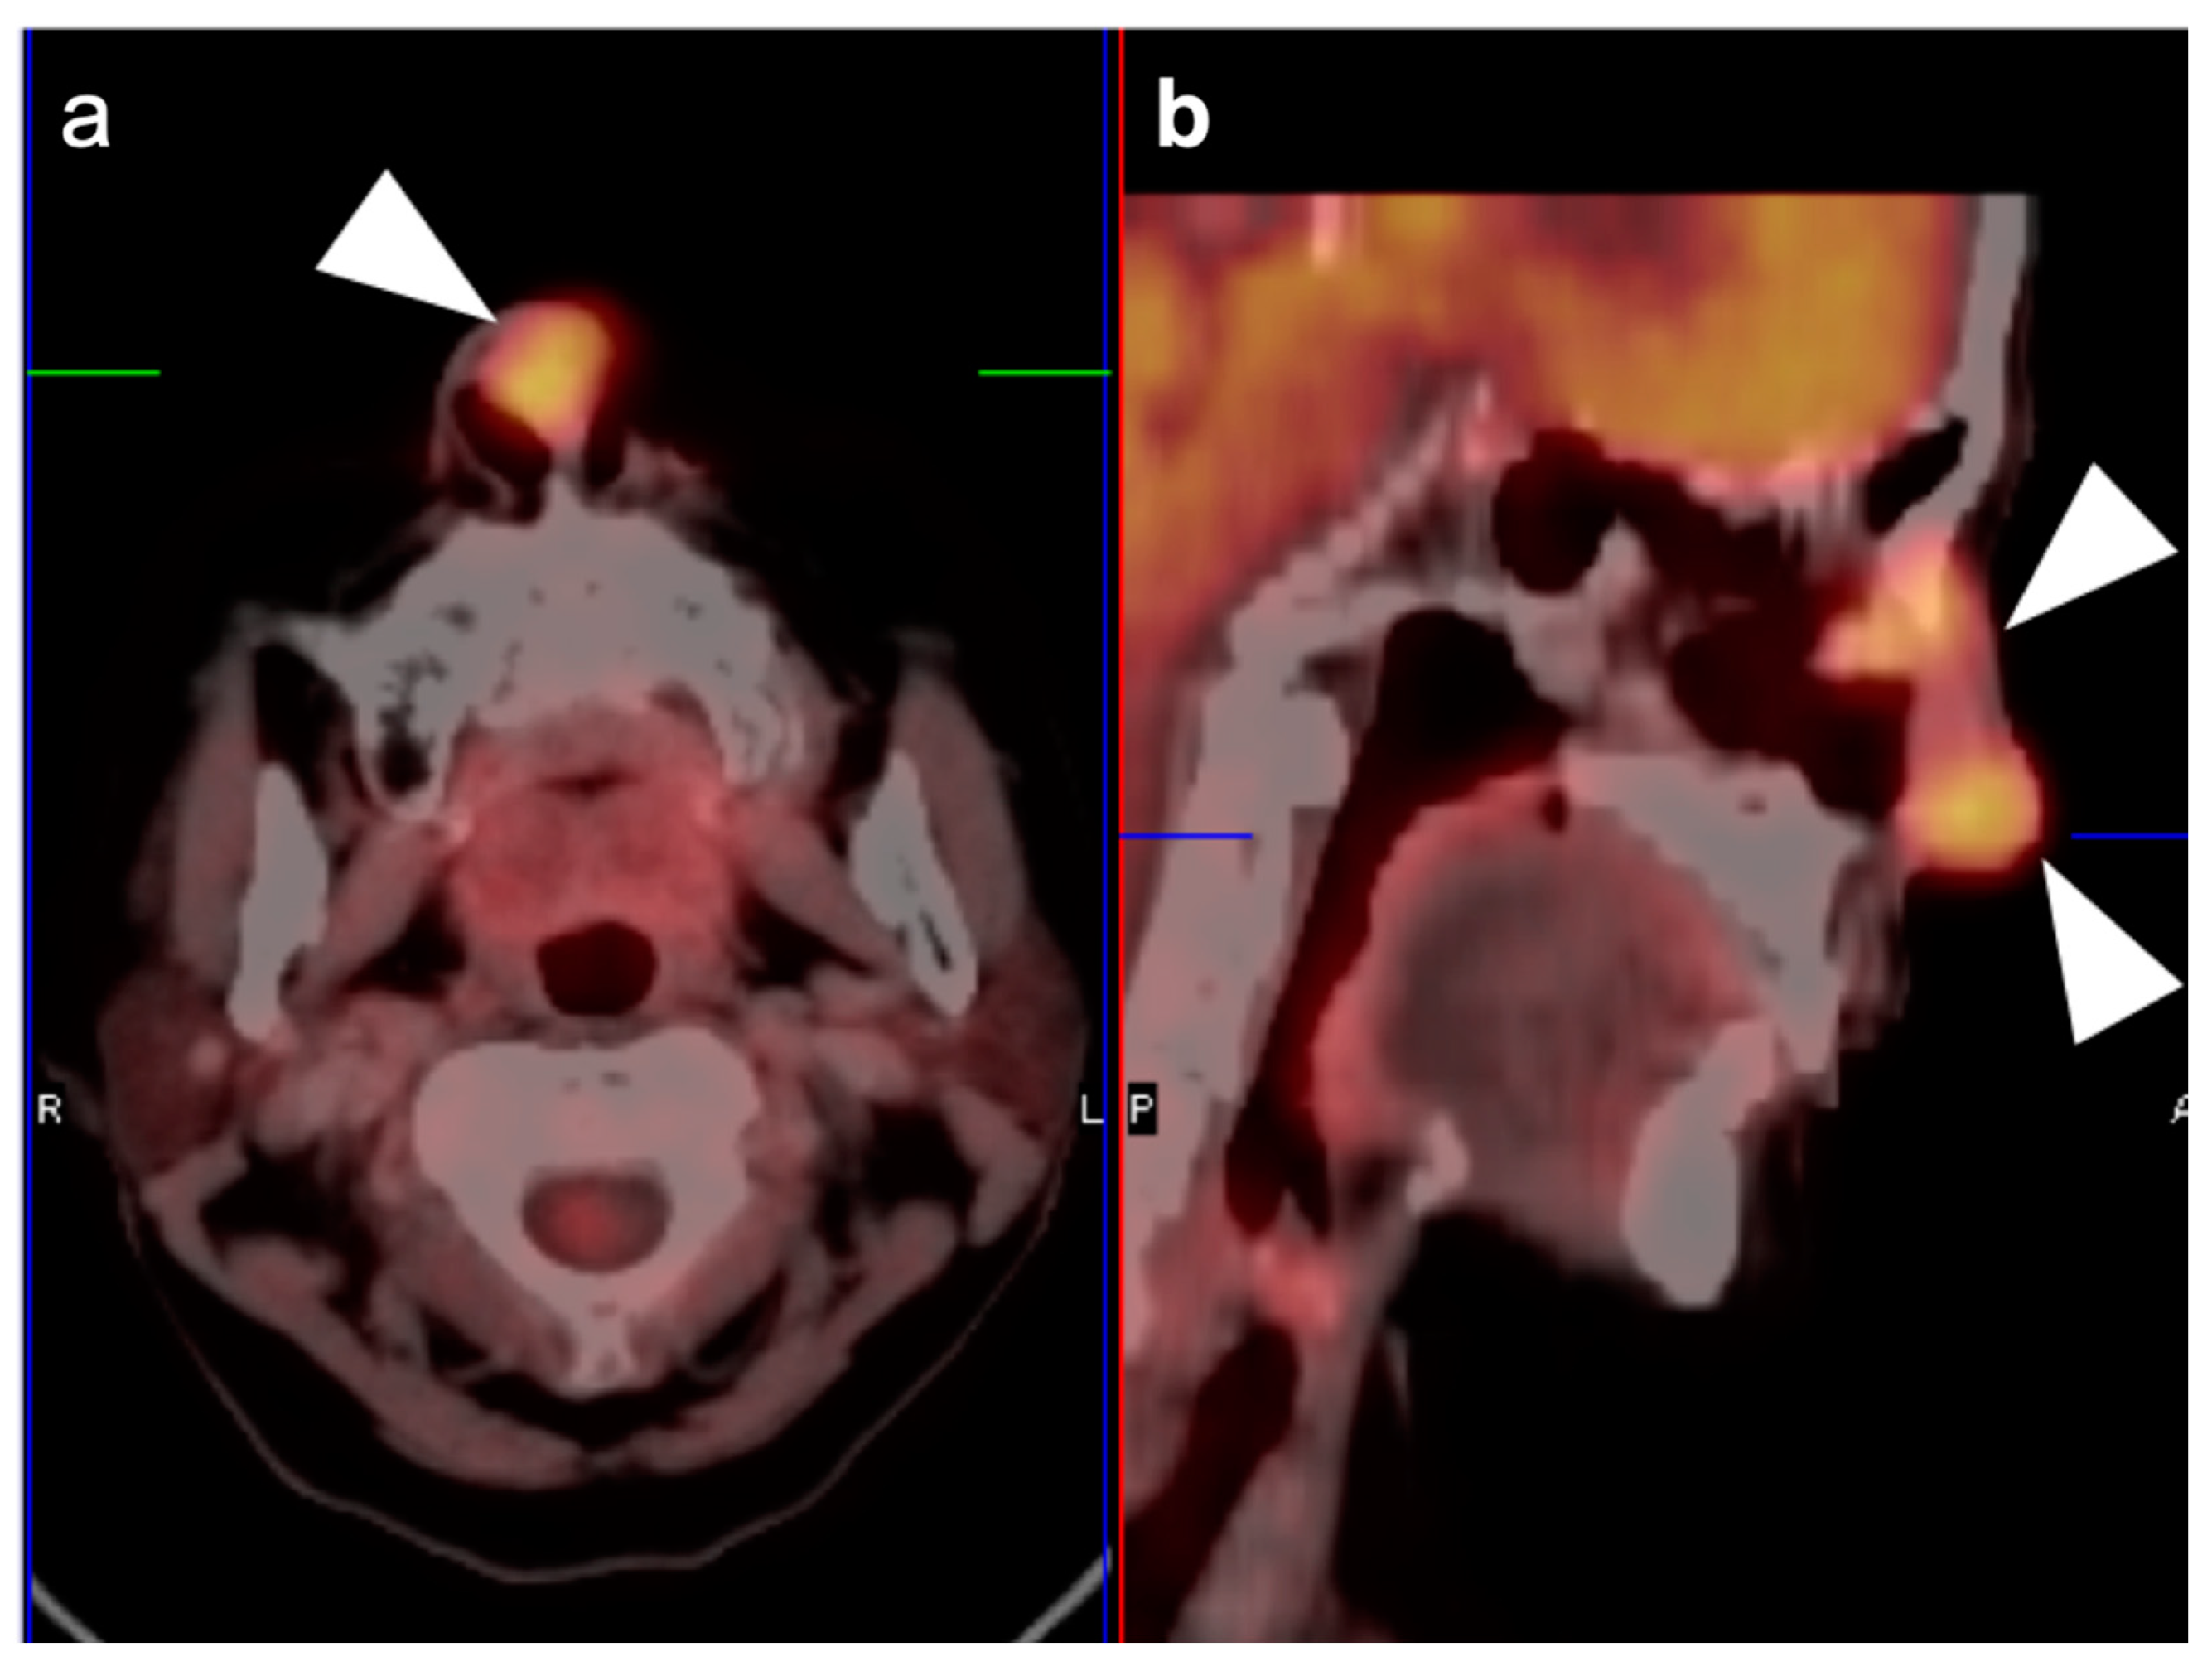

2.4. Sinonasal Tumors

- Esthesioneuroblastoma